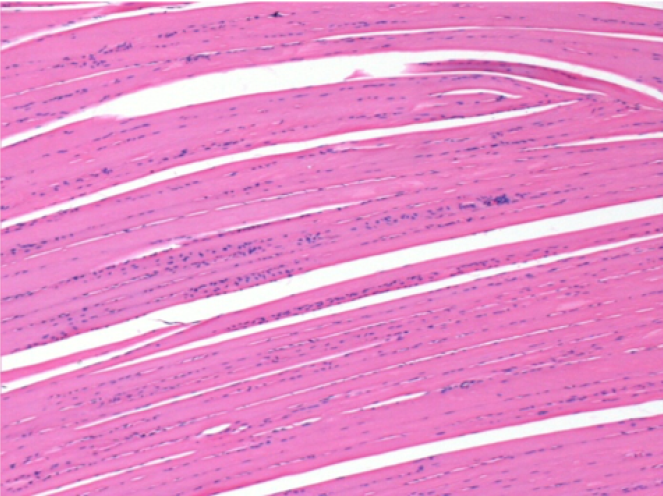

3 meses después de la inyección de Endopeel

3 meses (D90) después de la inyección de Endopeel 0.1ml en el músculo pretibial derecho.

L : Control-100xD90

R:100xD90